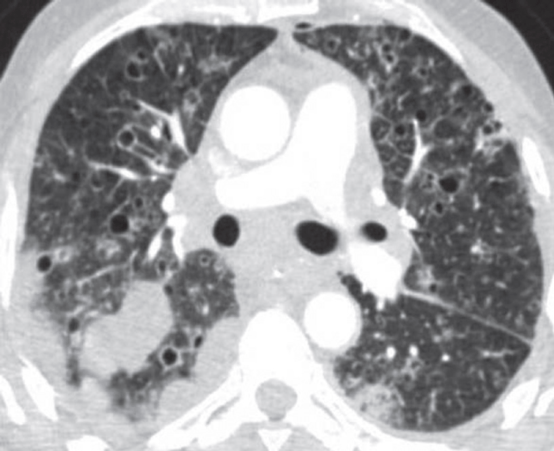

PLCH 最初的HRCT表现为小叶中心或细支气管周围结节,通常直径1-10毫米,边缘不规则。随着病情的发展,结节发生囊变。结节和囊肿常并存(图1A ),常可确诊。在晚期,囊肿占多数,数量和大小不一,不规则,形状各异,并可融合( 1B)。起初,囊肿的壁很厚,后来囊变薄。囊性病变主要发生在上叶,不累及肋膈区域( 1 c)。气胸发生率高达15%( 1D)(3,6) 推测囊肿是由细支气管壁炎症引起的气道扩张、结节空洞化或纤维病变牵引起的空腔扩大而形成。继发改变包括肺动脉高压,可以CT观测到如肺动脉干和左右肺动脉增

1 肺朗格汉斯组织细胞增多症的CT 表现A 上叶不规则囊肿和边缘不规则的小叶中央结节( ) B不规则薄壁囊肿( 轴位)C不规则囊肿主要在上叶,且不累及肋膈区域( 冠状面)D不规则囊肿,一些小叶中心结节,左侧气胸( 轴位)